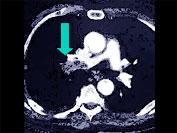

问题 该病人突发胸部疼痛,进行性呼吸困难,行X线片检查,提示右下肺病变,急诊CT平扫加增强,如图所示,则 ( )

选项 A.X线片示右下肺实变影 B.SCT增强扫描示右侧肺动脉主干完全性充盈缺损 C.右肺动脉开口处见不规则软组织密度影 D.考虑为右侧肺动脉(中央性)栓塞 E.考虑为右侧肺癌

答案 ABCD